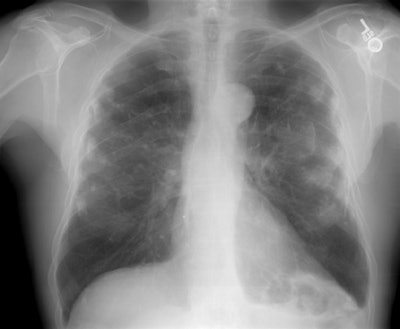

The patient below presented for evaluation of an abnormal CXR which demonstrated a left retrocardiac mass. (Click image to enlarge)